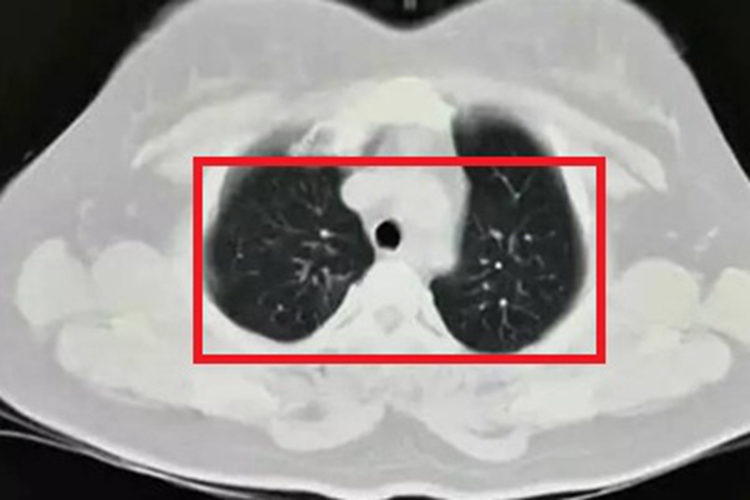

肺型组织胞浆菌病患者进行影像学检查时,可见局部有炎性浸润灶阴影和侵袭性空洞,呈孔状,还可伴有咳痰、咳嗽、发热、盗汗、胸痛等症状。